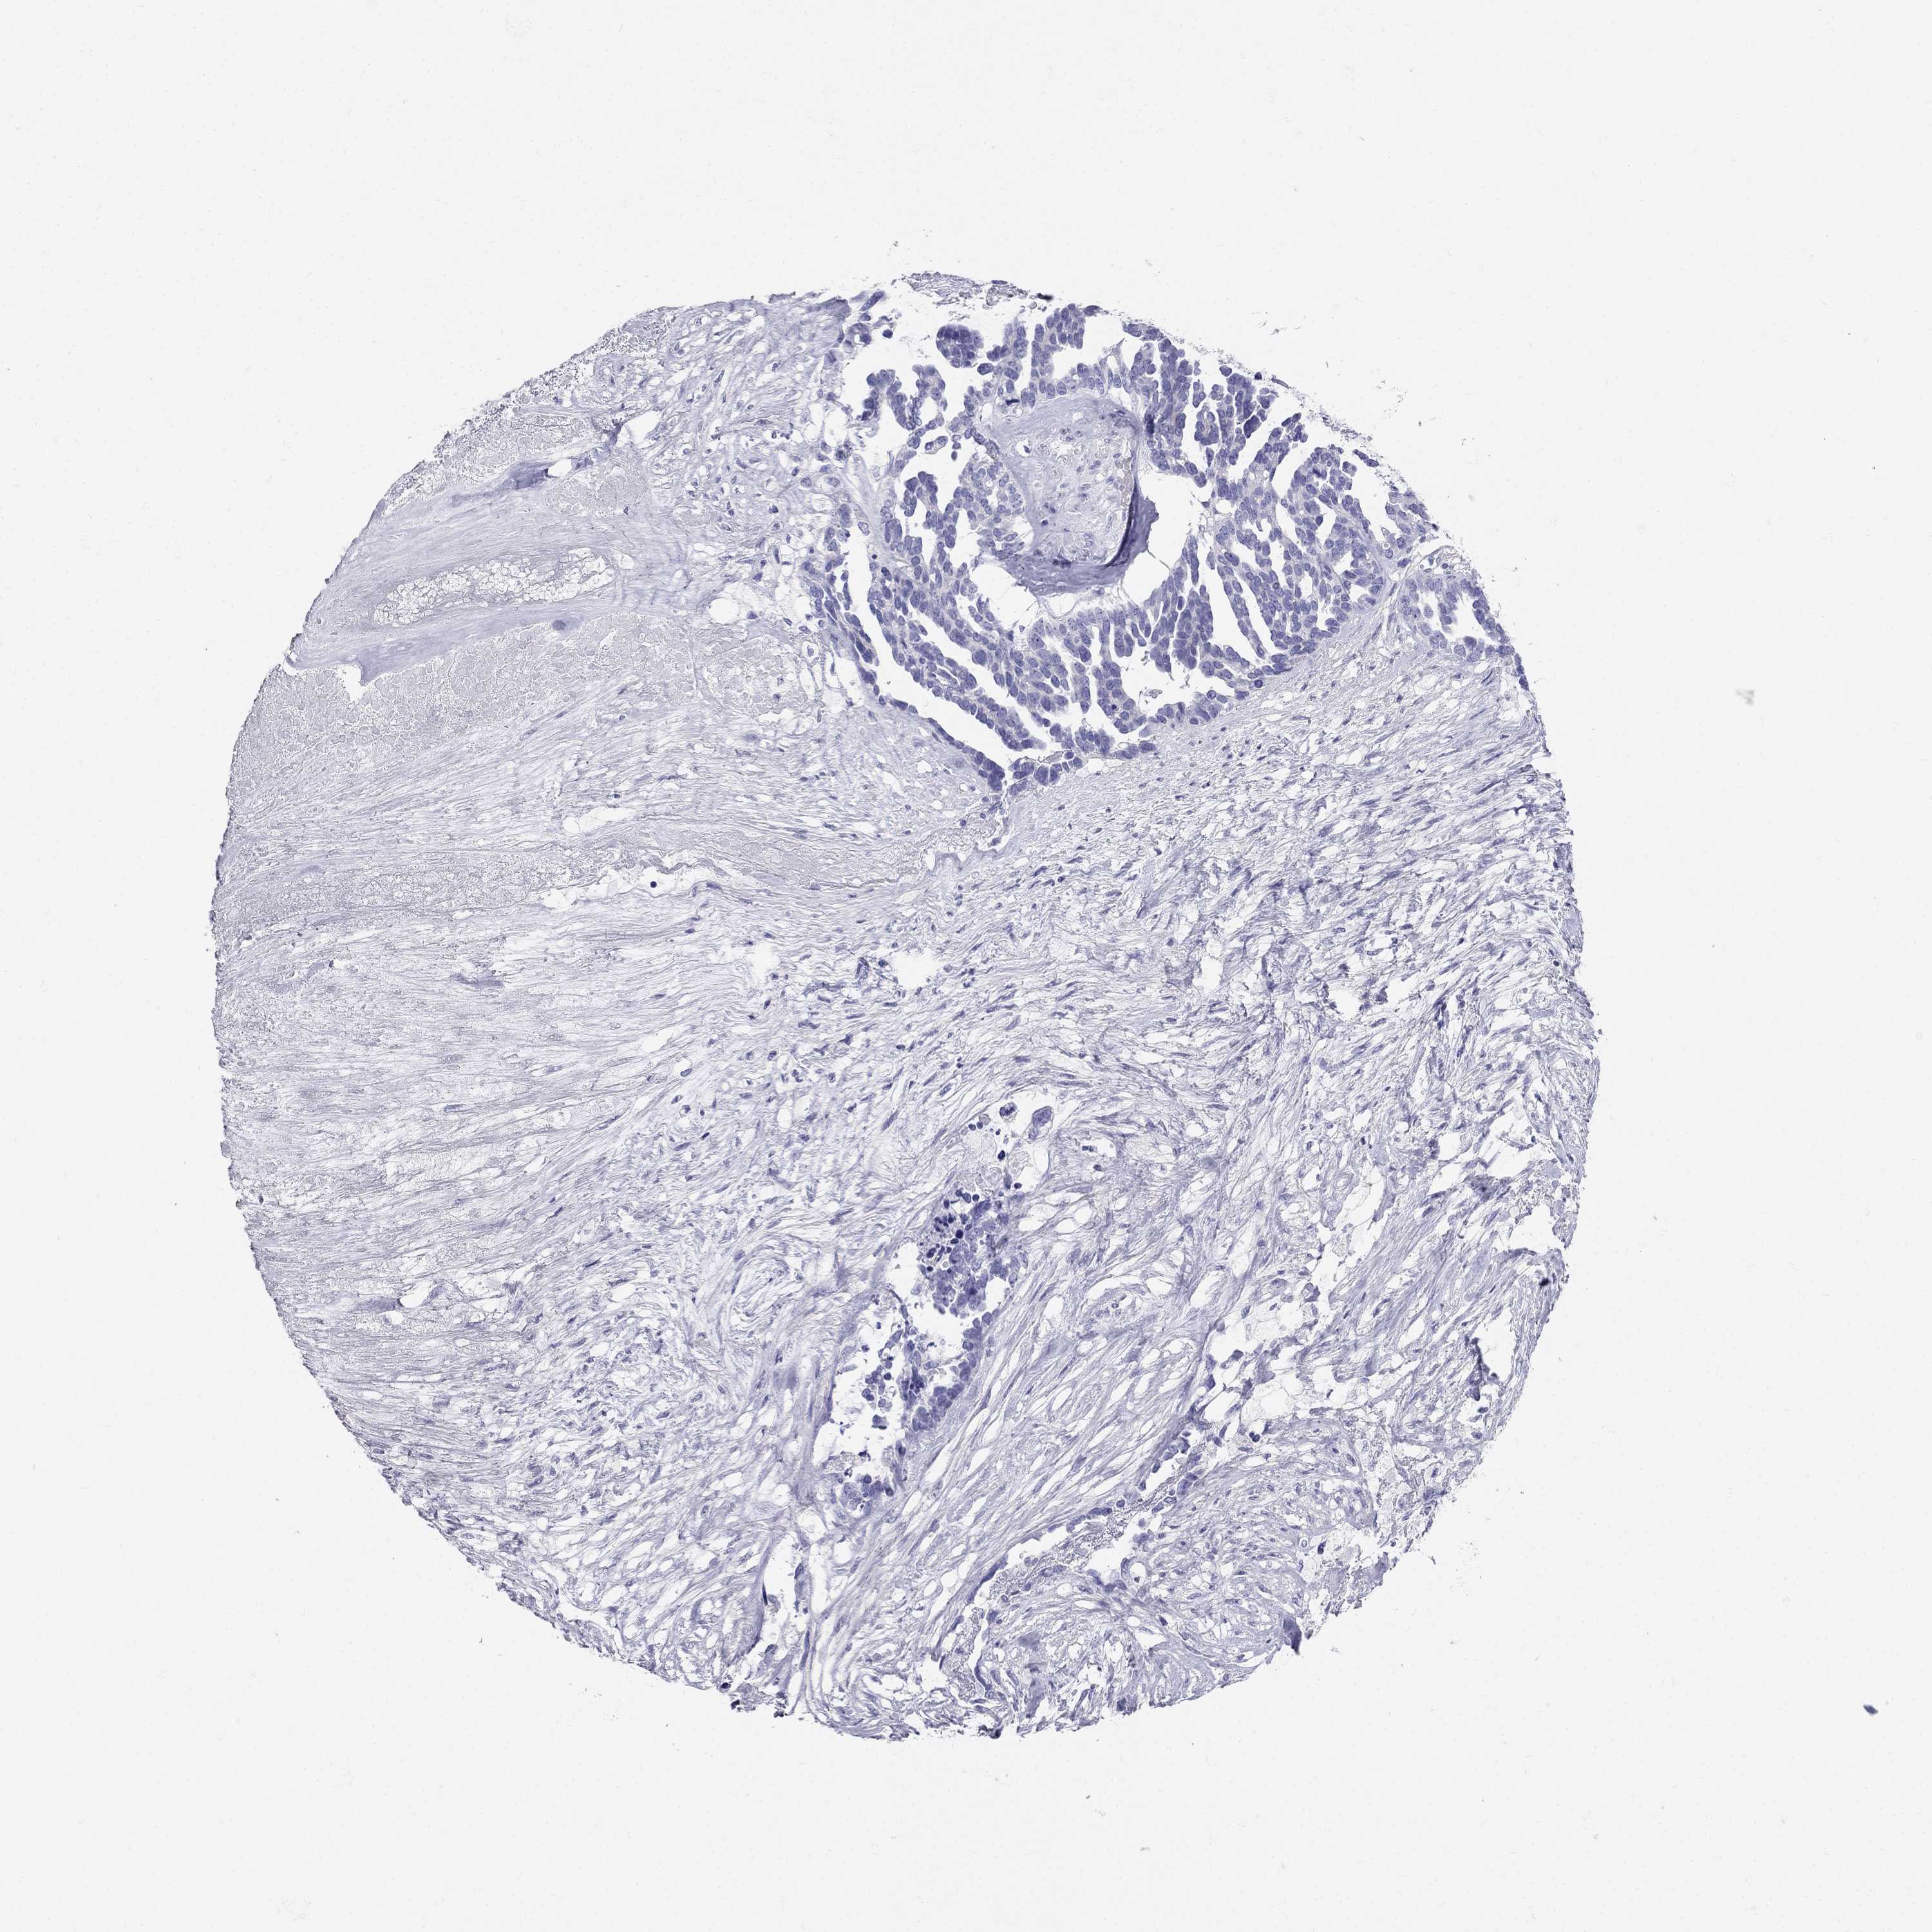

RFLNA